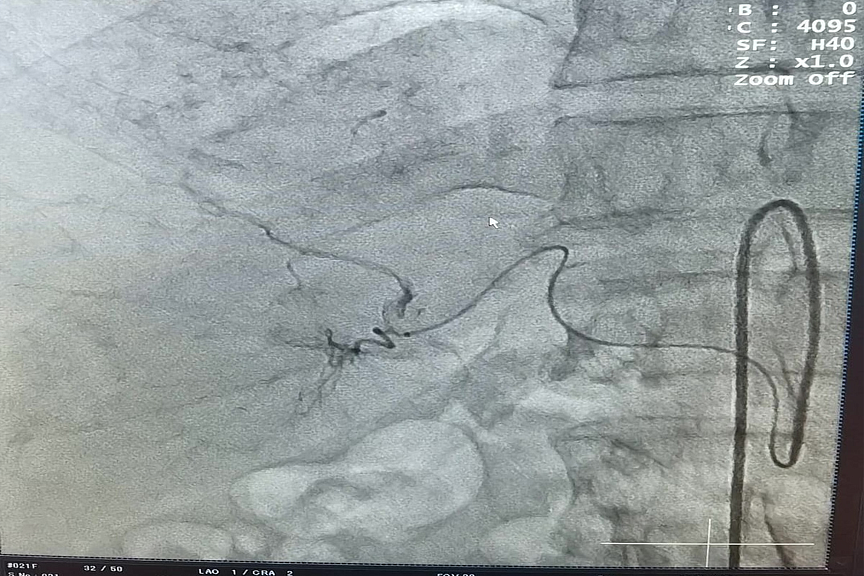

Фото: Амурский областной онкологический диспансер

Благодаря успешно освоенной методике лечения рака печени амурские хирурги выполнили важную манипуляцию для пациента. Доктора провели трансартериальную химиоэмболизацию - внутрисосудистый вариант химиотерапии, при котором через небольшой прокол в бедренную артерию вводится катетер, и далее опухоль атакуется химическим «зарядом» точно направленного действия. Об этом сообщается на сайте Амурского областного онкологического диспансера.

Под рентген-контролем врачи подвели катетер к печеночной артерии, перекрыли кровоток в сосуде, питающем злокачественное образование, специальными микросферами с химиопрепаратом. В результате чего прицельному воздействию лекарственного средства была подвергнута непосредственно опухоль. Её клетки, лишённые кровоснабжения, начали разрушаться, при этом для всего организма токсичность противоопухолевого препарата сведена к минимуму.

Операцию провели пациенту рентгенхирурги из двух учреждений Приамурья – Борис Васильев (Амурский областной онкологический диспансер) и Сергей Полянский (Благовещенская городская клиническая больница). Работали в эндоваскулярной операционной БГКБ, оснащенной ангиографом.